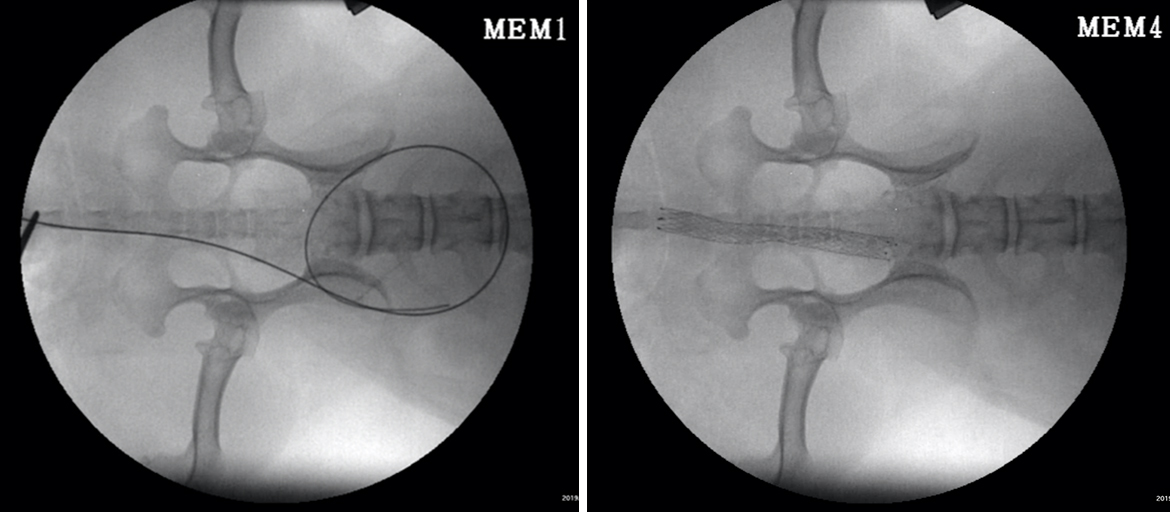

尿道ステント術とSUBを行った症例